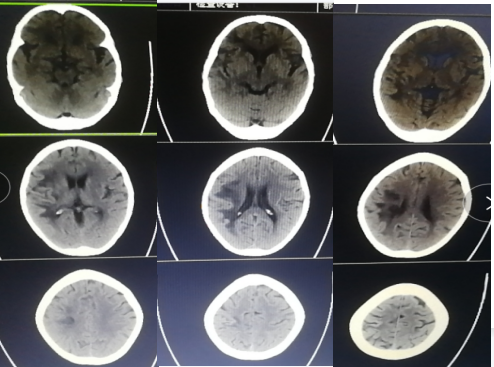

入院影像检查

头颅CT:

未见脑出血征象,右侧基底节区、颞叶、侧脑室体旁多发点片状低密度阴影。

头颅MRI:

(患者有金属义齿,核磁仅弥散相较清楚)未见脑出血征象,右侧基底节区、颞叶、侧脑室体旁多发点片状异常信号影。